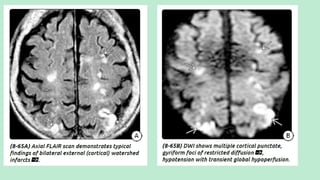

MRI: Multifocal peripheralT2/FLAIR hyperintensities. Hemorrhagic emboli

cause "blooming" onT2* sequences (most sensitive sequence: DWI).

Typical finding in multiple emboli infarcts: Small peripheral foci of

diffusion restriction in several different vascular distributions.

T1 C+ imaging may show multiple punctate enhancing foci.

Septic emboli often demonstrate ring enhancement, resembling